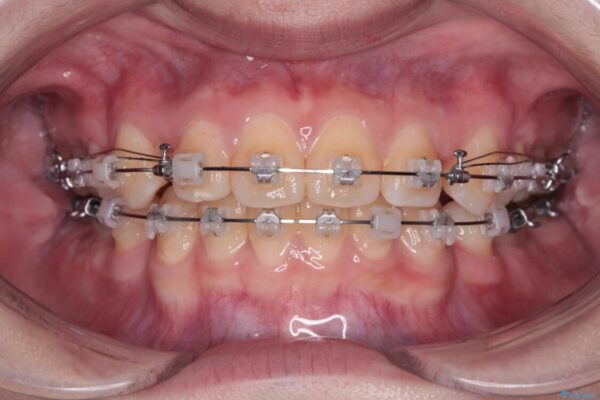

治療途中

• 転勤でも安心して治療継続 抜歯スペース閉鎖と深い噛み合わせ改善のワイヤー矯正 治療途中画像